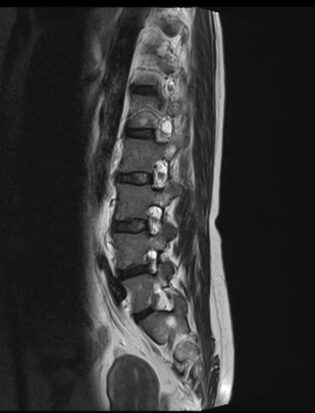

Resonancia Magnética de columna lumbar

“QUISTES PERINEURALES”

Los quistes perineurales son quistes llenos de líquido cefalorraquídeo en las raíces nerviosas, localizados principalmente en la zona sacra de la columna vertebral, aunque pueden encontrarse en cualquier sección de la columna vertebral; pueden causar una radiculopatía progresivamente dolorosa. Las mujeres se ven afectadas con mayor frecuencia que los hombres. Los pacientes con quistes perineurales presentan dolor en la zona de los nervios afectados por el quiste, debilidad muscular, dificultad para sentarse durante periodos prolongados, pérdida de la sensibilidad, pérdida de reflejos, dolor al estornudar o toser, inflamación en la zona sacra, parestesias, dolor de cabeza, ciática, y disfunción intestinal, de vejiga y sexual.

El diagnóstico se basa en la resonancia magnética.